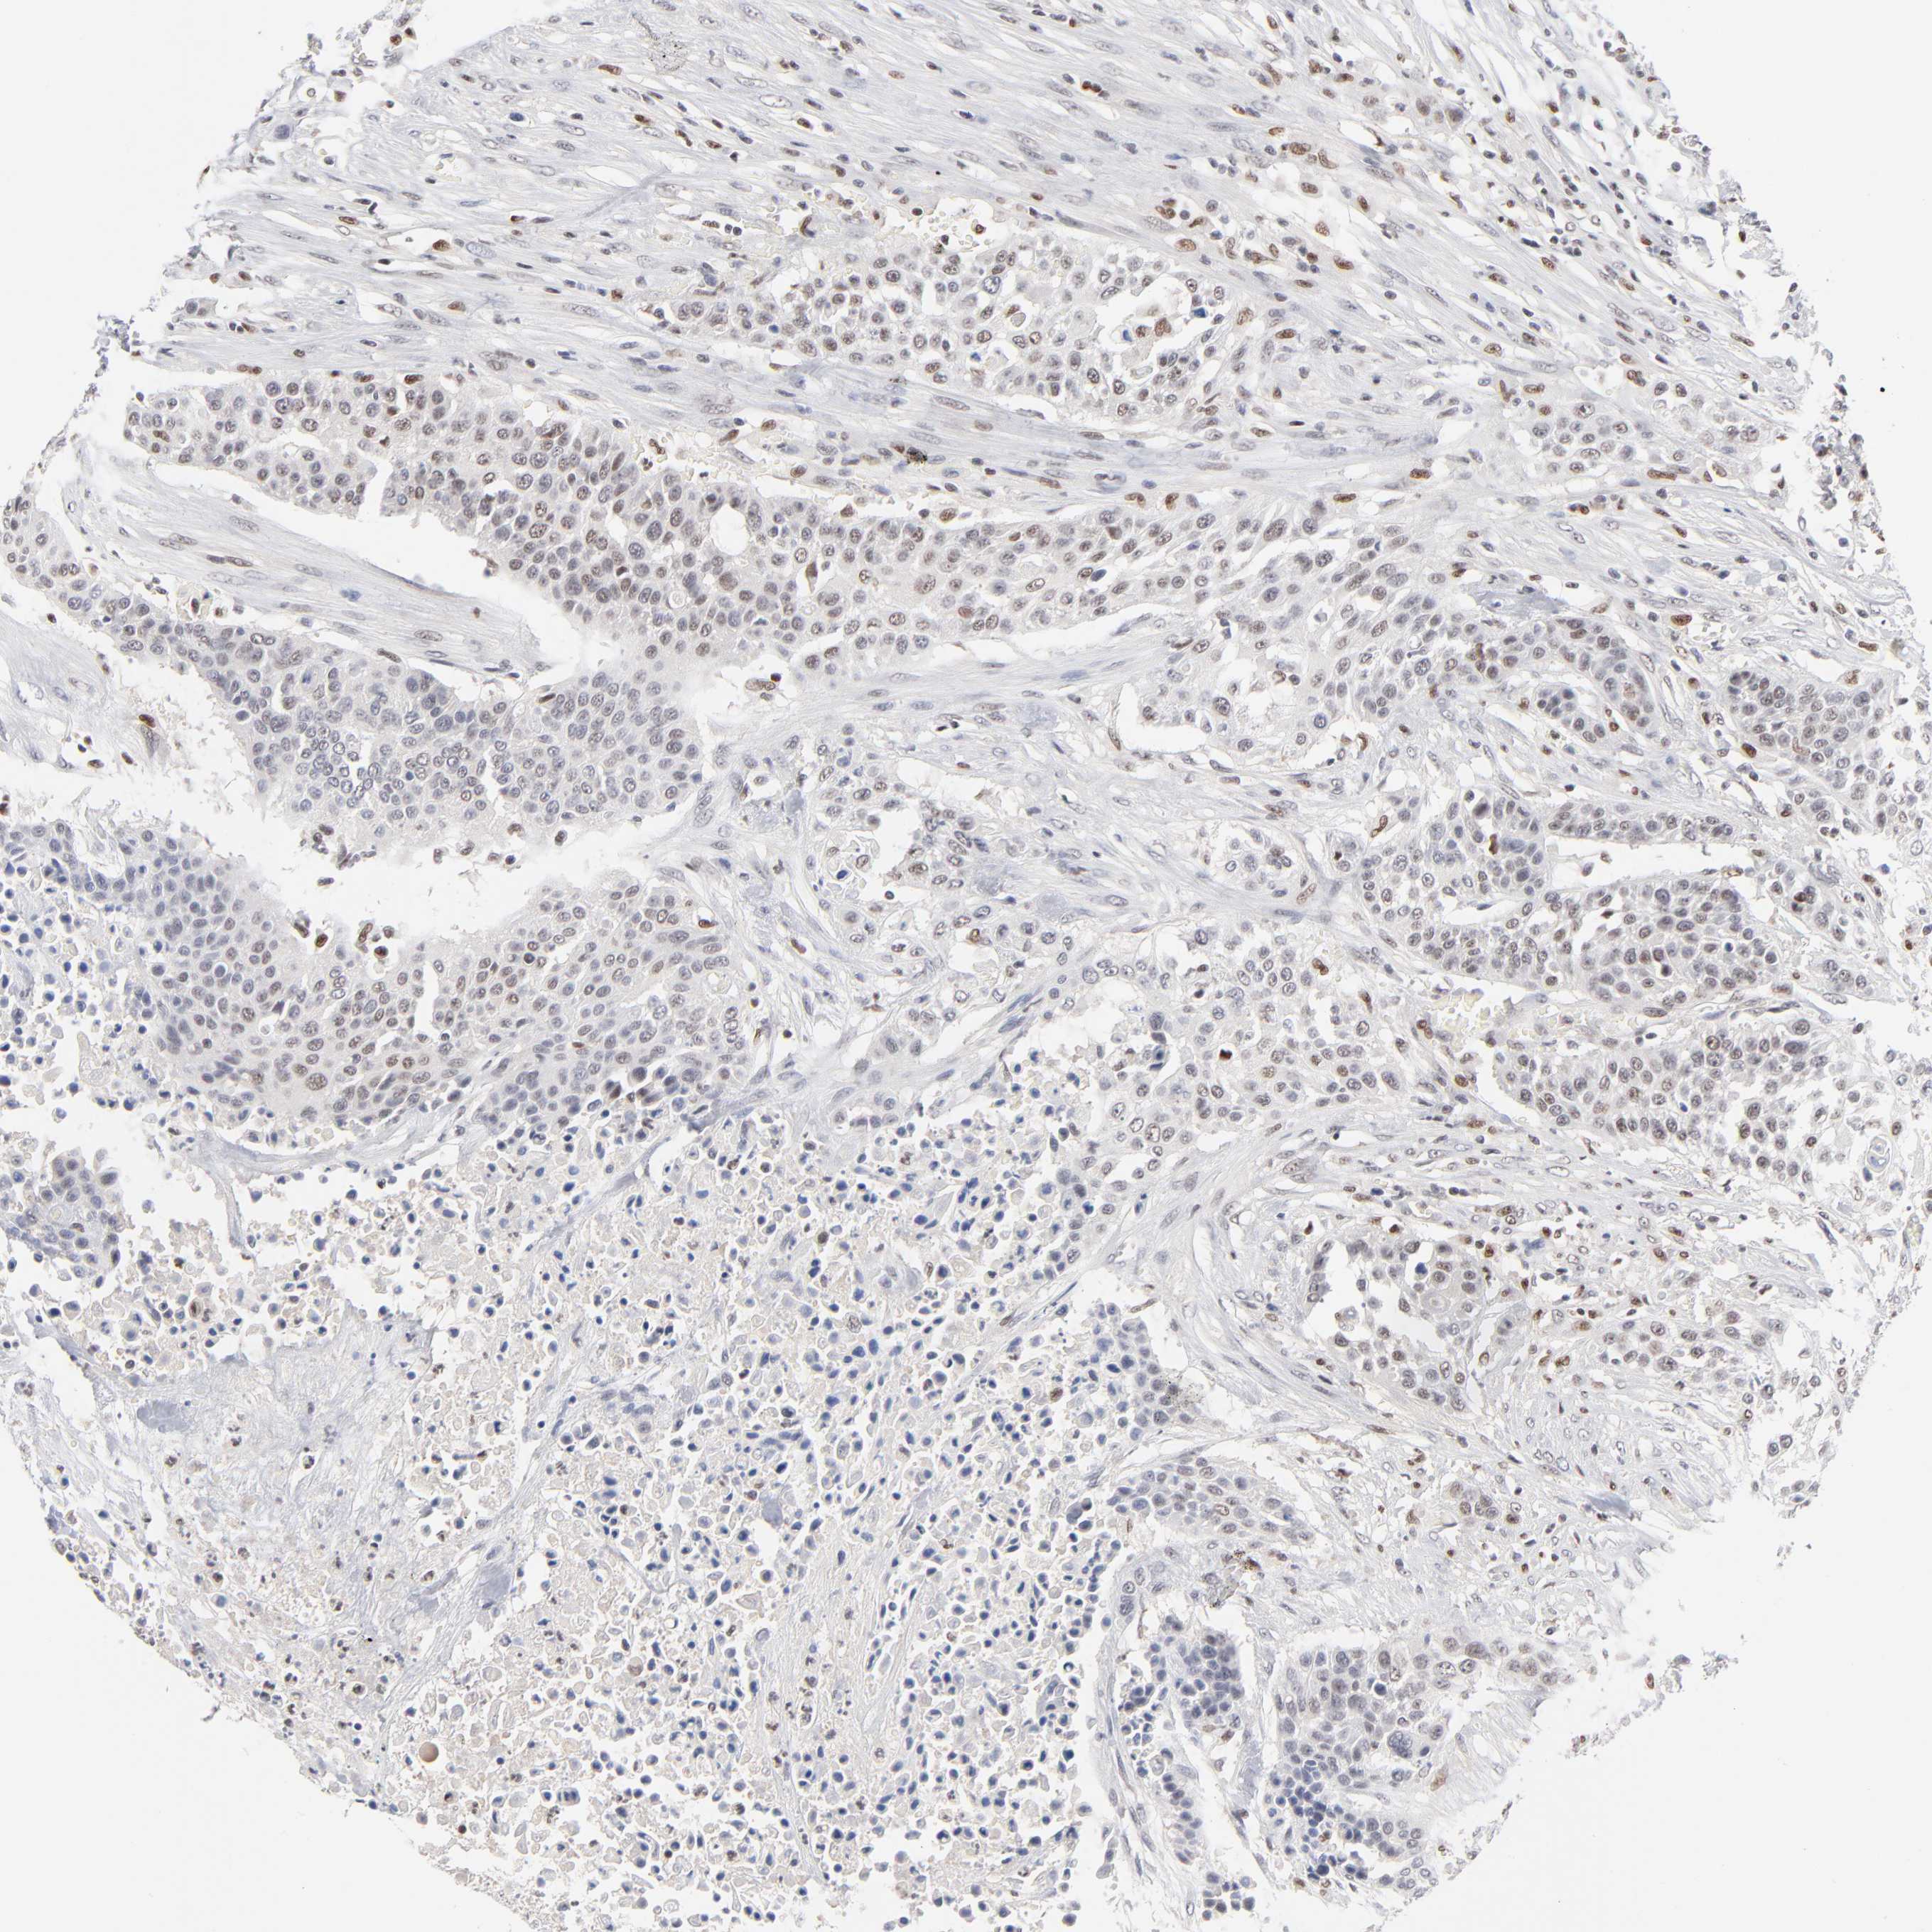

UROTHELIAL CANCER - Protein expressioni

A mouse-over function shows sample information and annotation data. Click on an image to view it in a full screen mode. Samples can be filtered based on level of antibody staining by selecting one or several of the following categories: high, medium, low and not detected. The assay and annotation is described here.

Antibody stainingi

Antibody staining in the annotated cell types in the current human tissue is reported as not detected, low, medium, or high, based on conventional immunohistochemistry profiling in selected tissues. This score is based on the combination of the staining intensity and fraction of stained cells.

Each image is clickable and will lead to virtual microscopy that enables deeper exploration of all samples and also displays staining intensity scores, fraction scores and subcellular localization as well as patient and tissue information for each sample.

Antibody HPA003474

Urothelial carcinoma, High grade